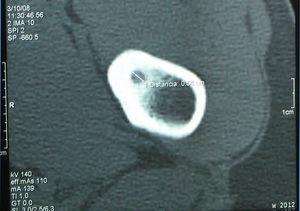

Se solicitaron radiografías de rodilla y pelvis. Las primeras fueron normales, pero en la metáfisis femoral, cercana a la cadera izquierda, se evidenciaba una osteopenia regional y una lesión con marcada esclerosis cortical y nidus central, compatibles con un osteoma osteoide (figura 1). El estudio con tomografía computarizada (TC) confirmó la presencia de un nidus de 5,4mm (figura 2). Se solicitó una consulta con el Servicio de Traumatología de nuestro hospital, que realizó una resección del nidus. El estudio anatomopatológico confirmó el diagnóstico. Cuatro meses tras la intervención, el paciente está asintomático y la movilidad de ambas caderas es normal, aunque persiste una discreta atrofia en el muslo izquierdo, con un perímetro 2cm menor.

Figura 2. Tomografía computarizada de fémur: engrosamiento cortical y nidus de 5,4mm.